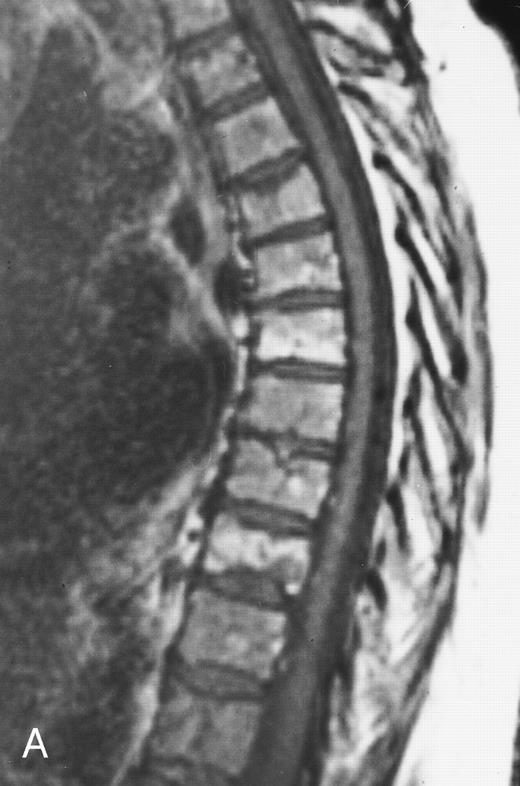

Diffuse MR pattern of abnormal marrow in a 29-year-old man with AML: T1-weighted sagittal (500/10, TR/TE) (A), T2-weighted, fat-suppressed fast spin echo sagittal (5000/96, TR/TE, ET 16) (B), and enhanced T1-weighted sagittal (500/10, TR/TE) (C) MR images of the thoracic spine. The abnormal vertebral bodies in (A) are dark and isointense to the intervertebral discs and in (B) they become bright. In (C), the abnormal marrow enhances and the vertebrae become brighter than the discs. Note extraosseous mass (arrowheads) in the posterior epidural space with preservation of the bony cortex.